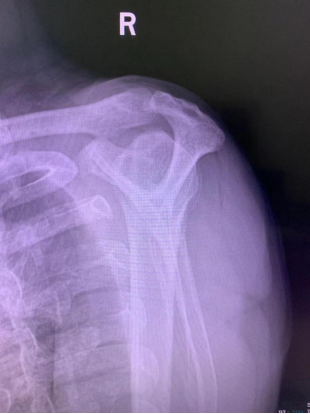

与其他检查手段比,X线检查的优点为直观、低成本、快速。肩关节X线检查首选肩关节正位、Y位,能清晰的显示肩峰形状和冈上肌出口位的形态。肩峰下骨赘形成,是肩峰下间隙狭窄的重要原因。间隙底部为肱骨头,顶部为喙突、肩峰以及连接两者的喙肩穹。由于这种结构关系,当有骨赘及III型肩峰存在,当运动者做上臂后伸,也就是上肢外展这个动作时,它就对肩袖组织造成一次撞击,从而产生肩袖损伤。

肩关节Y位III型肩峰

X线检查可表现为肩峰前缘硬化,肩峰下表面骨刺形成,肱骨大结节硬化或骨赘形成。如果X线片发现问题,可以再进行CT或者核磁共振(MRI)检查。CT扫描三维重建,显示肩关节结构更为清楚、直观,可观察X线片不易发现的关节内骨。核磁共振(MRI)对软组织分别率高,可显示肩袖病变。